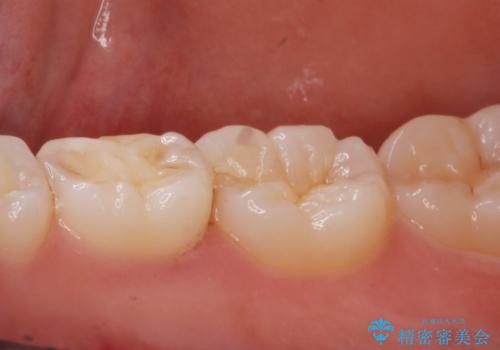

レントゲンを撮影したところ虫歯がありましたので拡大鏡下で虫歯を取り除いた後、e-maxインレーにて治療を行いました。

手前の歯は乳歯でしたが、患者様と相談しなるべく長持ちさせたいとの事でしたのでe-maxインレーでの治療となりました。

適合の良い詰め物が入りました。